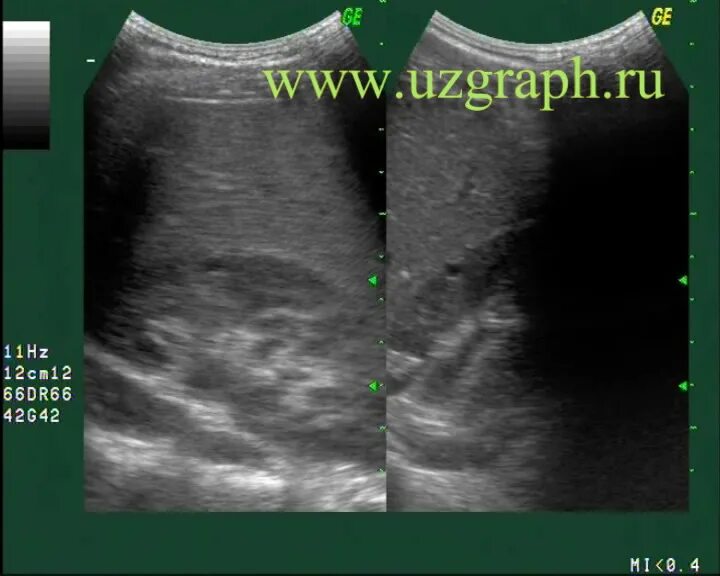

Можно вылечить кисту почки